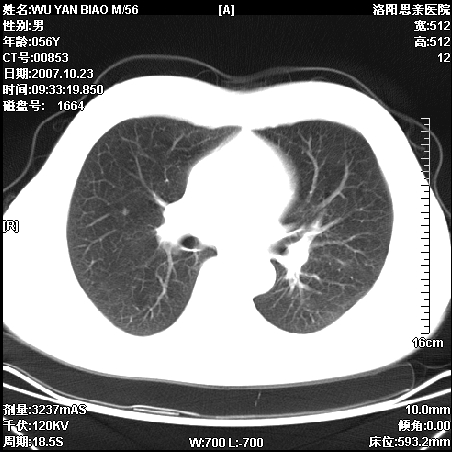

标题: CT10160:M56Y,体检发现,病人无不适,病人随访中 [打印本页]

标题: CT10160:M56Y,体检发现,病人无不适,病人随访中

后上纵隔占位,与肺交界清,宽基底附着脊柱,密度均匀,局部骨质无明确改变.

考虑;神经源性肿瘤,---起源交感n链?,不除外肠源性囊肿.

1、病灶在后纵隔脊柱旁沟内,此处是神经原性肿瘤的好发部位

2、病灶边缘光滑整齐,更说明病灶来于纵隔,由于有胸膜的包裹所以才导致这么光滑的边缘

3、病灶内的密度均匀